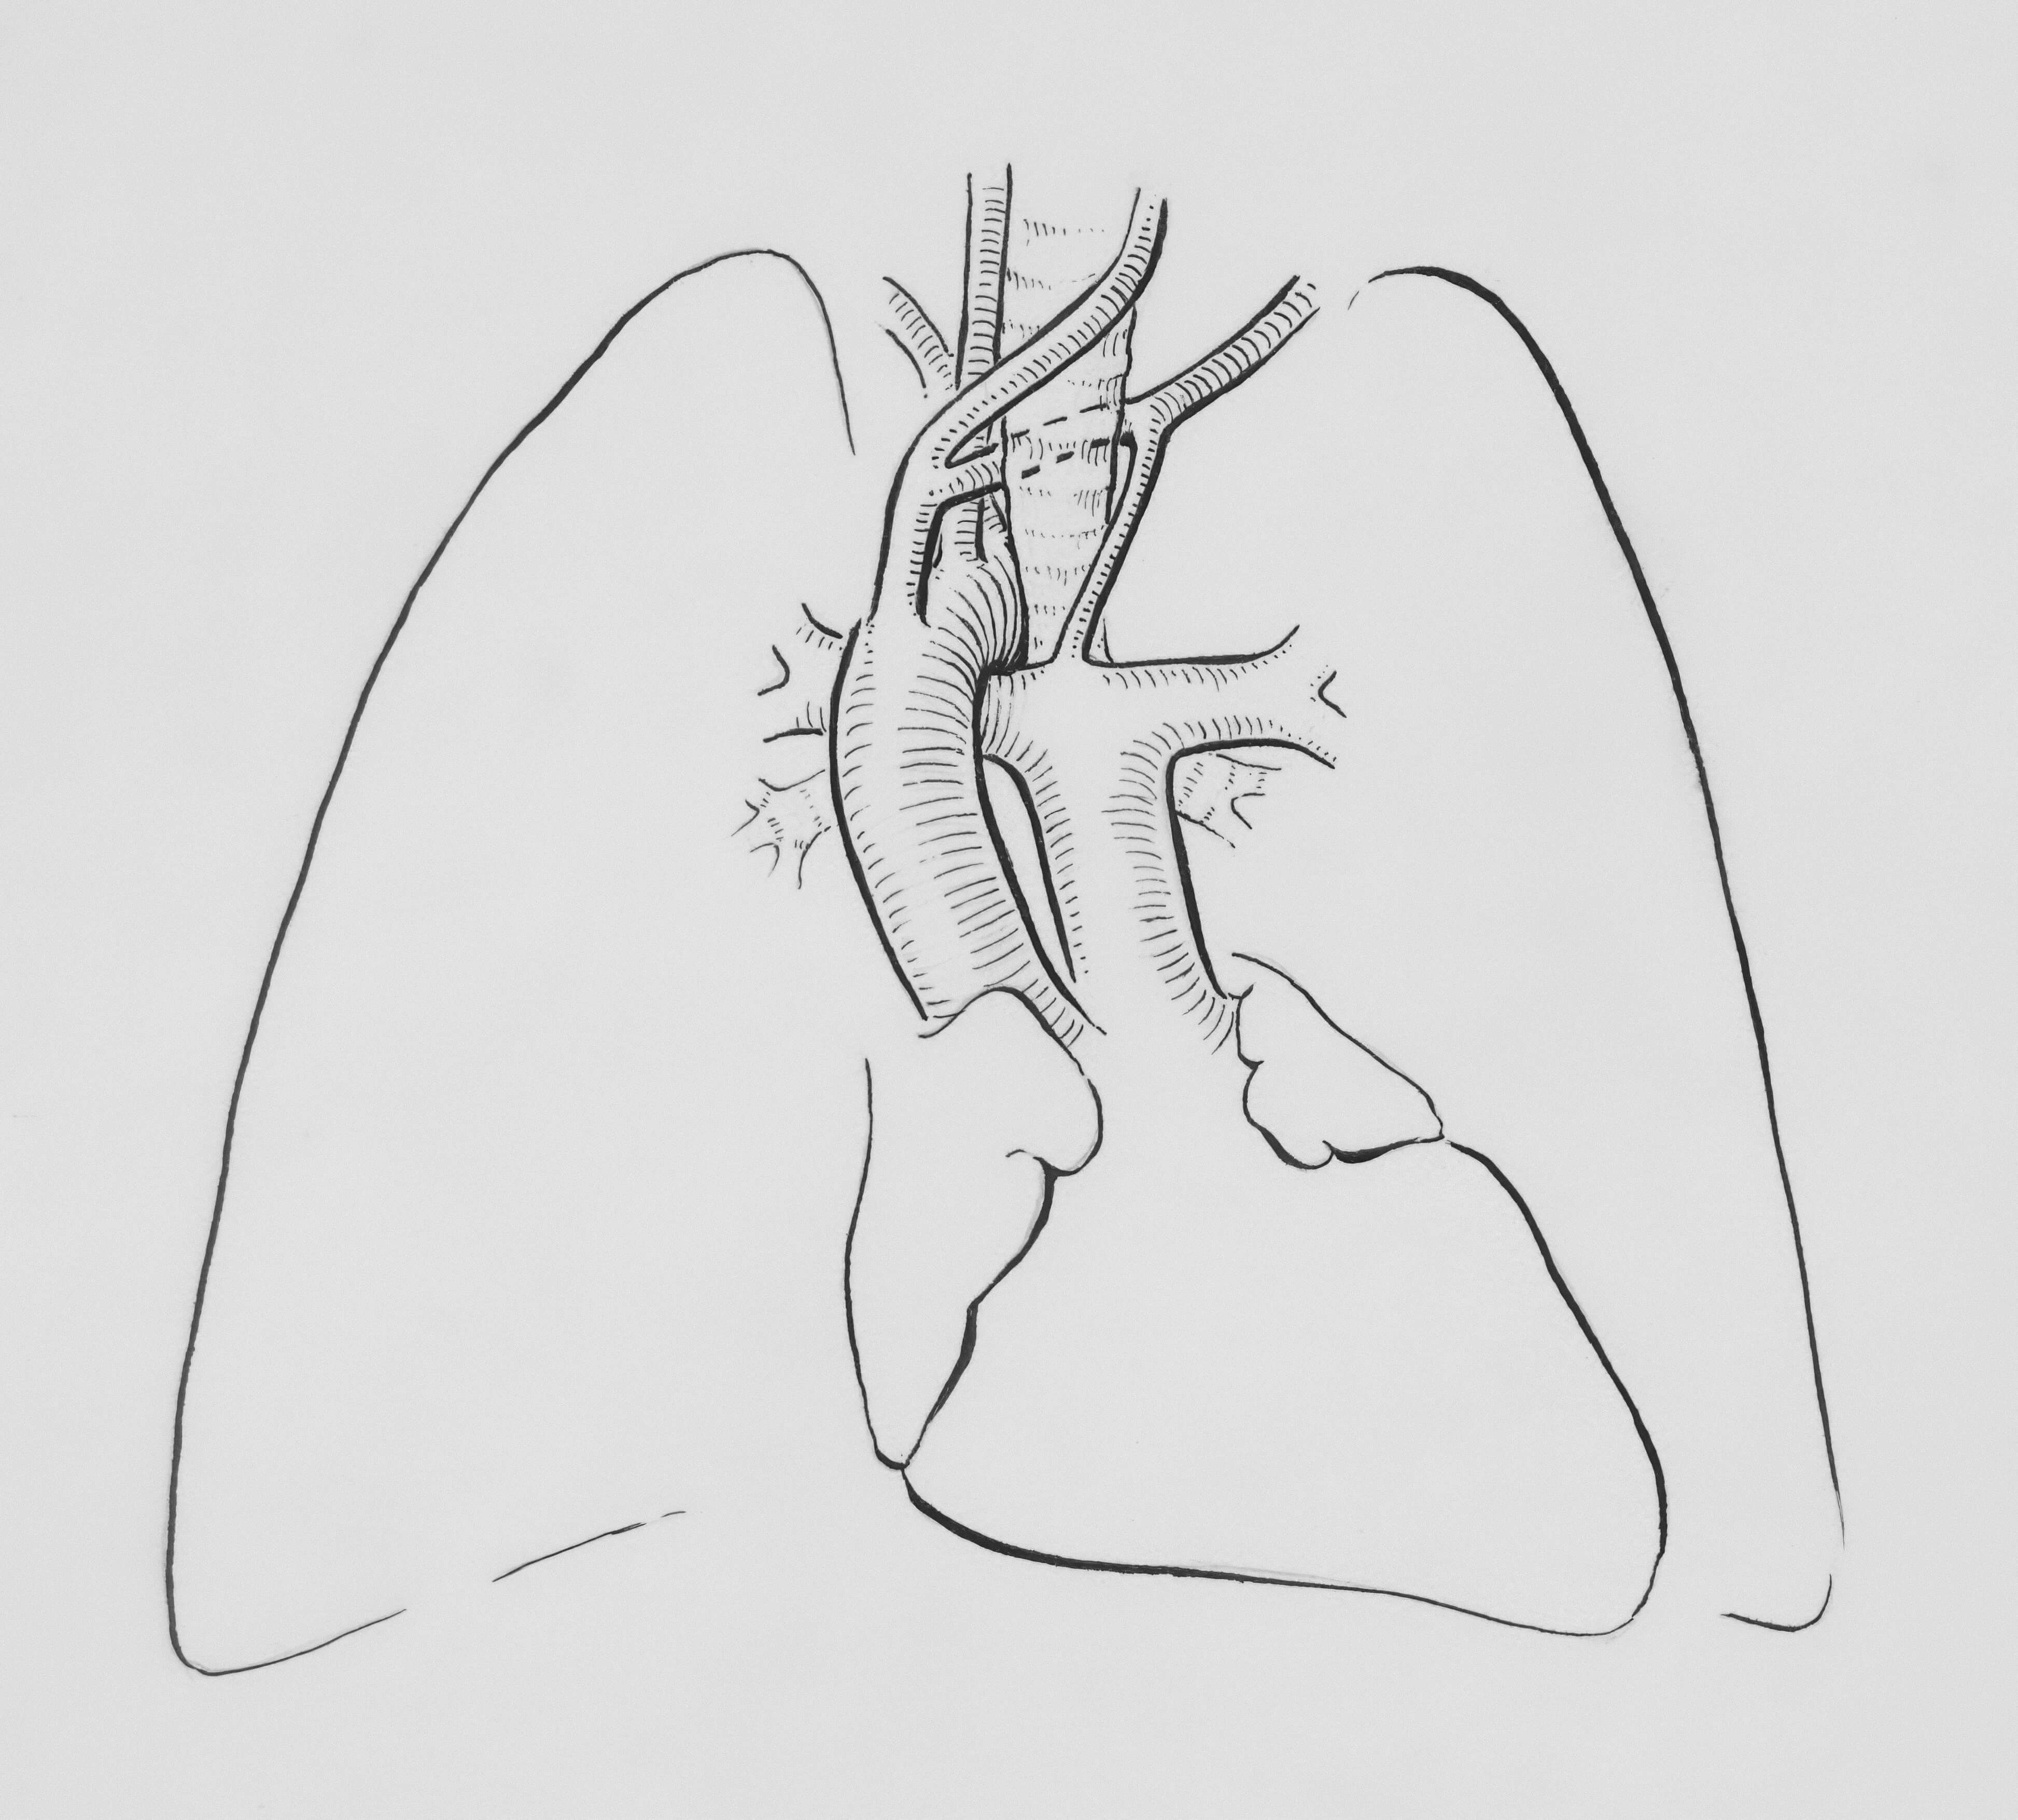

폐기흉(공기가슴증)은 폐의 표면에 구멍이 생겨 늑막강(가슴막 사이의 공간)에 공기가 들어가면서 폐가 쭈그러드는 질환입니다. 특히 키가 크고 마른 젊은 남성에게 자주 발생하며, 적절한 치료를 받지 않으면 생명에 위험할 수 있습니다.

건강한 사람의 늑막강은 음압을 유지하여 폐가 팽창된 상태를 유지하는데, 기흉이 발생하면 이 균형이 깨져 폐가 수축하게 됩니다.

- 가슴 X선 촬영

- 가장 기본적인 진단 방법

- 폐 허탈 정도 확인